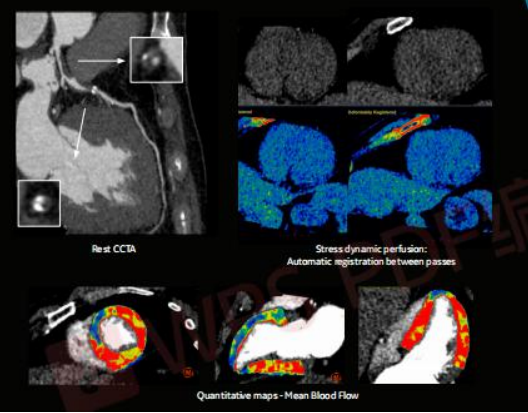

全心肌灌注成像

APEX CT在心脏检查方面,完全革新了以往的复杂检查流程:不需要控制心率,不受心律变化影响,甚至不需要控制呼吸。患者完全在自然状态下接受检查,只需在一个心跳内就完成了整个心脏 CT扫描,这对疑难冠脉病变、血管变异、先天性心脏病等疾病的治疗,都有着重要的意义。

在世界卫生组织公布的全球十大致死病因中,心血管疾病常年处于首位。APEX CT可以开展头颈心联合扫描,对排查早期斑块,提前预防斑块脱落造成的脑部血管阻塞具有重要意义。心脏每分每秒都在运动,如何能够在快速的运动中,得到稳定且清晰的图像?心脏CT扫描一直是难点,常规的心脏CT检查需要一套复杂的流程,患者常常需要先服用控制心率的药物,还需要进行屏气训练,儿童患者还需要进行镇静……而对于高心率、心律失常、无法屏气和需要介绍全身血管扫描成像的患者,CT扫描更是难上加难。

不仅如此,APEX CT对微小病灶的检出能力也显现出无与伦比的优势。传统 CT 扫描心脏冠脉,只能看到一级二级的血管,而 APEX CT可以看到三级、四级,甚至更小的分支;传统CT对直径1毫米以下的血管很难拍出清晰图像,而 APEX CT却可以做到,这意味着能看到更多的微小病灶。